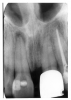

In Figure 4, recurrent caries appears at the mesial of tooth #3 and #4, and the distal of tooth #28. Also, note areas of interproximal caries on teeth #5-6.

Figure 4 - Recurrent Caries

Figure 4